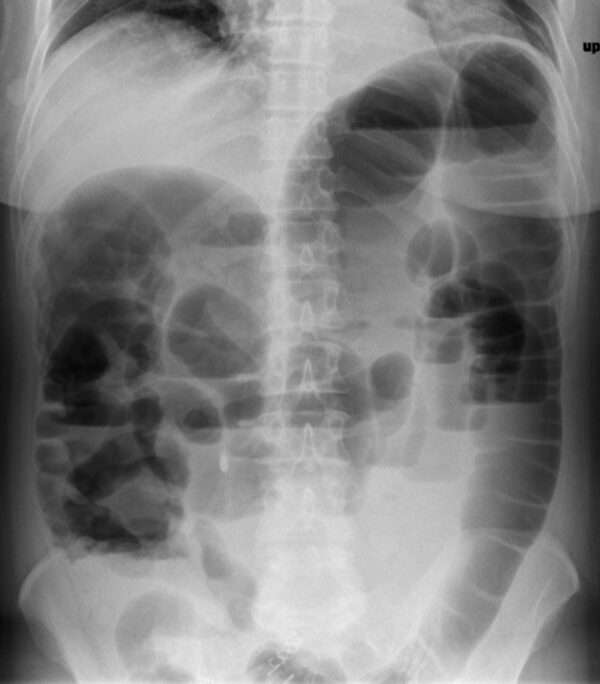

Pseudoobstrucción aguda del colon (síndrome de Ogilvie)

La dilatación masiva espontánea del ciego y del colon proximal es un fenómeno que puede presentarse en diversos contextos clínicos en pacientes hospitalizados, y es una condición que puede desencadenar…